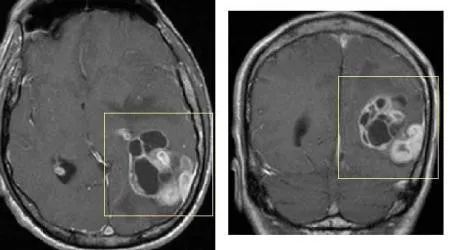

神经胶质瘤(画框所示)的MRI影像学图片